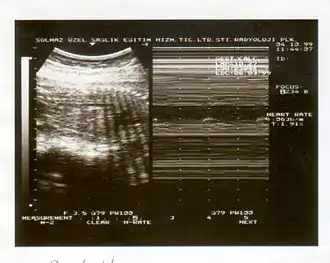

A biophysical profile (BPP) is a prenatal ultrasound evaluation of fetal well-being involving a scoring system,[1] with the score being termed Manning's score.[2] It is often done when a non-stress test (NST) is non reactive, or for other obstetrical indications.

The BPP has five components: four ultrasound (US) assessments and an NST. The NST evaluates fetal heart rate and response to fetal movement. The five discrete biophysical variables are:

1. Fetal heart rate

2. Fetal breathing

3. Fetal movement

4. Fetal tone

5. Amniotic fluid volume